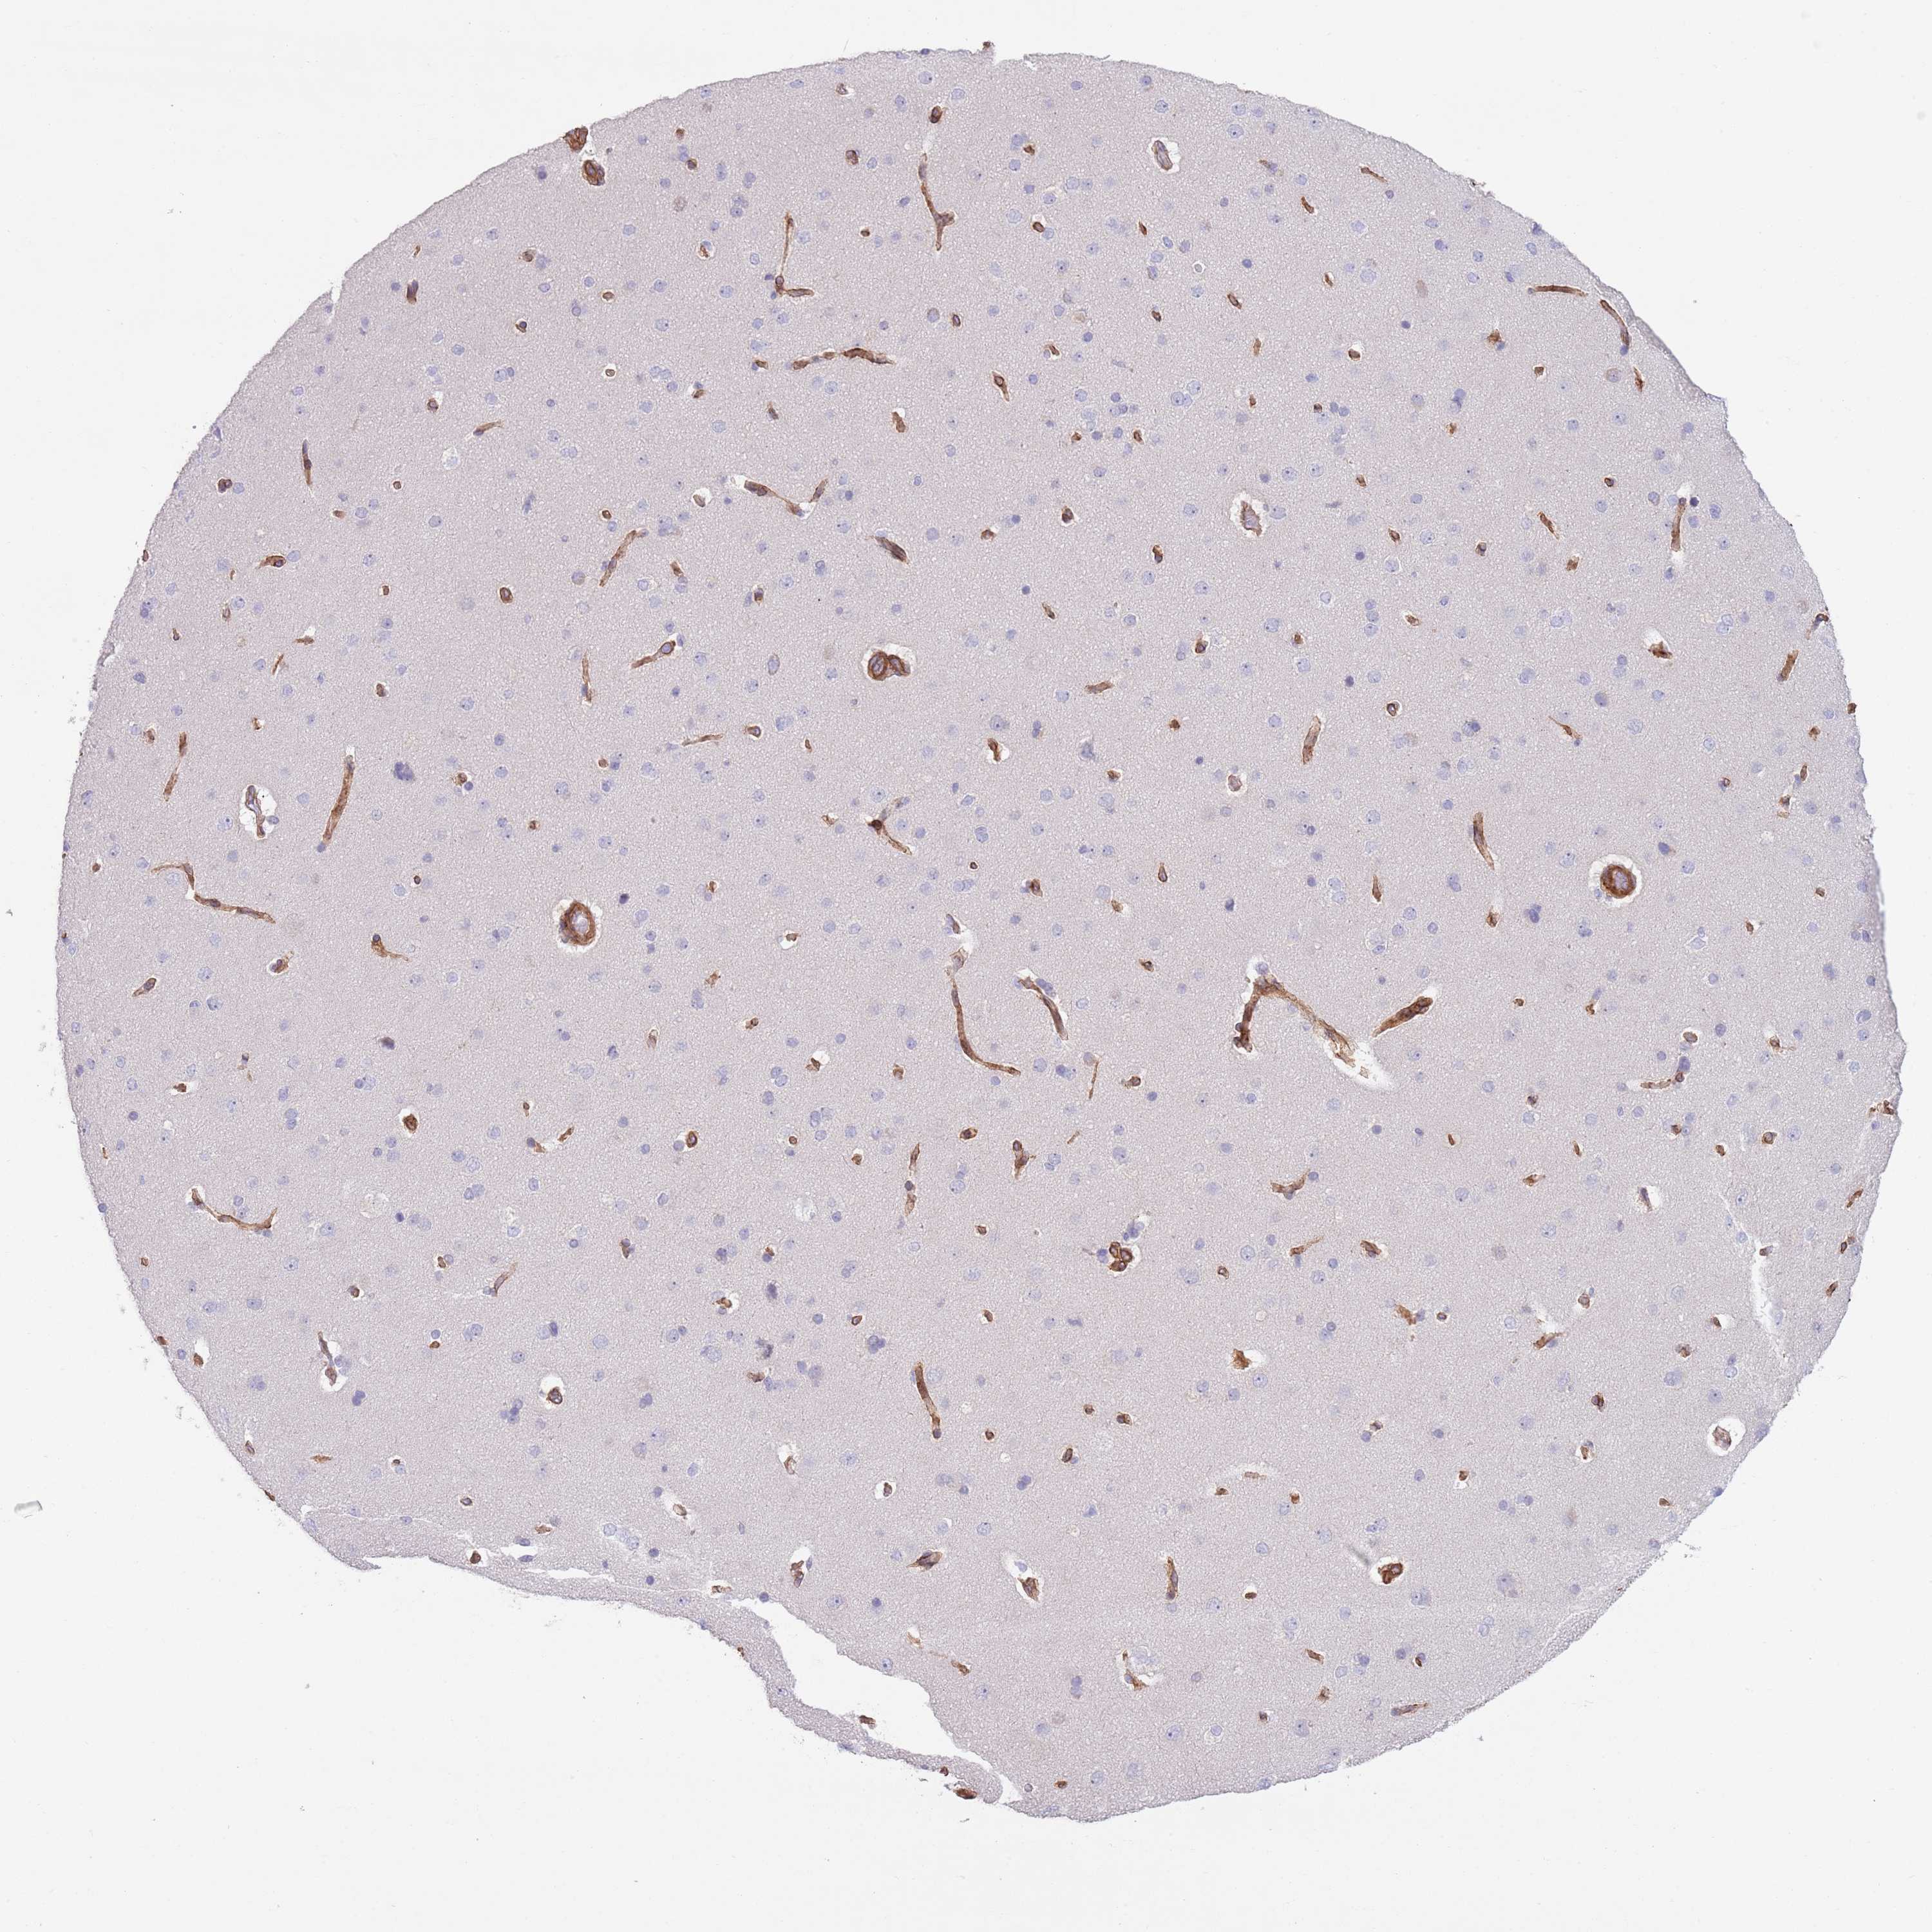

TINAGL1